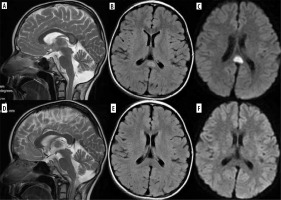

Vigabatrin is another AED known to cause brain abnormalities, most commonly occurring in the youngest patients, in the first year of life, especially with higher doses. Clinically, these abnormalities are usually asymptomatic. Brain MRI reveals symmetric T2 hyperintensities and diffusion restriction in the globi pallidi, thalami, dorsal brainstem, and dentate nuclei (Figure 2). These findings regress after vigabatrin withdrawal [11]. Without knowledge of this drug and its effects on the brain, one can consider MR images of the brain as similar to other rare diseases, such as Leigh syndrome, in which epilepsy can also occur [12].

Figure 2

An 11-month-old boy with epilepsy and trisomy 21 treated with vigabatrin. Consecutive DWI sections show a symmetrical pattern of thalamic, globi pallidi, anterior commissure, mamillary bodies and dorsal brain stem diffusion restriction, typical of vigabatrin side effects. D’ shows low apparent diffusion coefficient (ADC) values indicative of true diffusion restriction